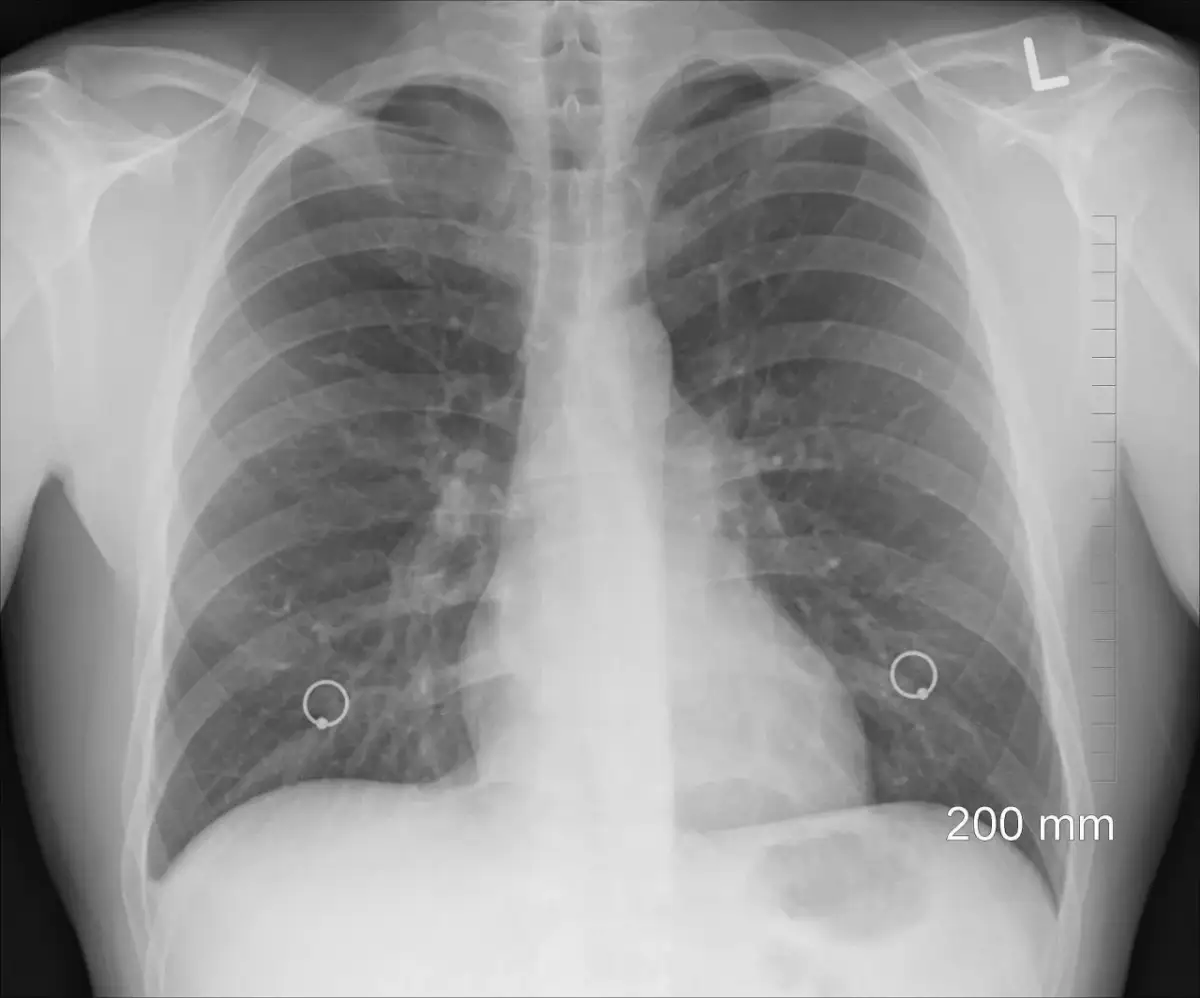

Rozstrzenie oskrzeli to przewlekła choroba płuc, która prowadzi do nieprawidłowego rozszerzenia oskrzeli. Wczesne rozpoznanie jej objawów jest kluczowe, aby uniknąć poważnych komplikacji zdrowotnych. Objawy tej choroby mogą być różnorodne i często rozwijają się stopniowo, co sprawia, że ich zignorowanie może mieć poważne konsekwencje. Dlatego tak ważne jest, aby być świadomym sygnałów, które mogą wskazywać na rozwijającą się chorobę.

Objawy rozstrzenia oskrzeli mogą ewoluować z czasem, co jest istotne dla monitorowania stanu zdrowia pacjenta. Na początku choroby objawy mogą być łagodne i sporadyczne, jednak z biegiem lat mogą ulegać pogorszeniu. Przewlekły kaszel, duszność oraz odkrztuszanie plwociny stają się coraz bardziej uciążliwe, co wpływa na jakość życia pacjenta. W miarę postępu choroby, pacjenci mogą również doświadczać zaostrzeń, które mogą prowadzić do hospitalizacji.

Warto zauważyć, że objawy mogą się również zmieniać w odpowiedzi na nawracające infekcje dróg oddechowych. Każda infekcja może prowadzić do dalszego uszkodzenia oskrzeli, co z kolei przyspiesza postęp choroby. Często pacjenci z rozstrzeniem oskrzeli doświadczają także innych powikłań, takich jak niedotlenienie czy zmiany w strukturze płuc, które mogą prowadzić do poważnych problemów zdrowotnych. Dlatego tak ważne jest regularne monitorowanie objawów i współpraca z lekarzem w celu dostosowania leczenia.